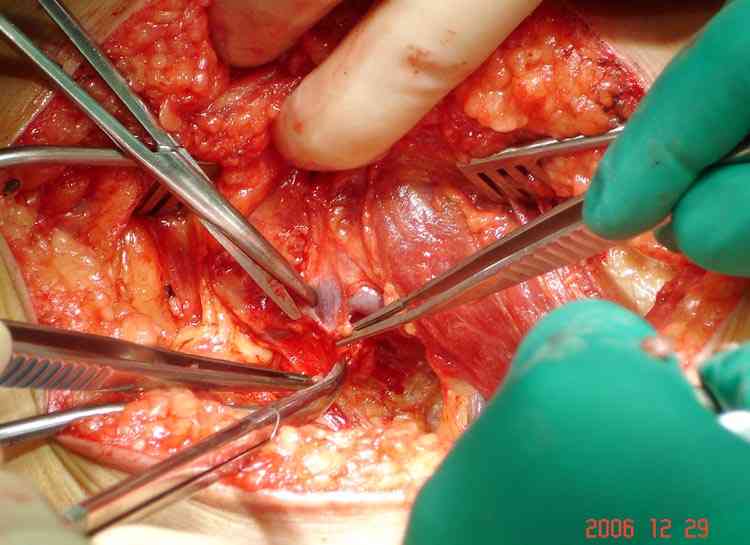

áÎÇÉÏÇÒÁÆÉÑ ÐÏÄÔ×ÅÒÄÉÌÁ ×ÁÓËÕÌÑÒÎÕÀ ÁÎÅ×ÒÉÚÍÕ × ÒÅÚÕÌØÔÁÔÅ ÄÁ×ÌÅÎÉÑ

ÜËÚÏÓÔÏÚÏÍ. óÏ×ÍÅÓÔÎÏ Ó ÓÏÓÕÄÉÓÔÙÍ ÈÉÒÕÒÇÏÍ ÂÙÌÁ ÐÒÏ×ÅÄÅÎÁ

ÐÌÏÓËÏÓÔÎÁÑ ÒÅÚÅËÃÉÑ Ó ÄÁÌØÎÅÊÝÉÍ ×ÏÓÓÔÁÎÏ×ÌÅÎÉÅÍ ÓÏÓÕÄÁ ×ÅÎÏÚÎÙÍ

ÇÒÁÆÔÏÍ.

éÍÑ     : #14 vascular work 6.jpg

ôÉÐ     : image/jpeg

òÁÚÍÅÒ  : 50108 ÂÁÊÔÏ×

ïÐÉÓÁÎÉÅ: ÏÔÓÕÔÓÔ×ÕÅÔ

Url     : http://weborto.net:8080/pipermail/ortho/attachments/20080403/4b5e6a95/attachment-0008.jpg